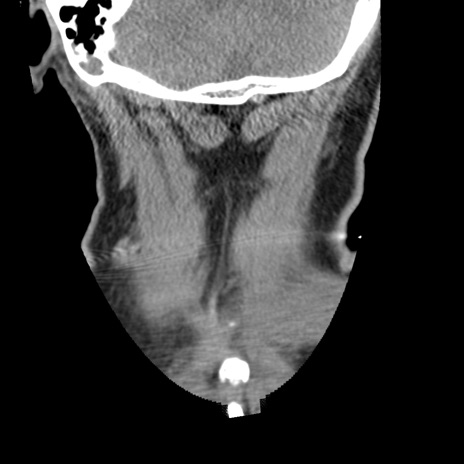

症例50 頚椎CT(冠状断像)

【症例】60歳代女性

【主訴】後頭部〜右後頸部にかけての痛み

【現病歴】本日飲食店でコーヒーを飲んでいたところ、突然後頭部〜右後頸部にかけて痛みが出現し、右上肢の感覚障害を伴ったため救急要請。

【身体所見】脳神経学的に明らかな異常所見を認めず。右上肢に軽度の感覚障害あり。

異常所見と診断は?

横断像